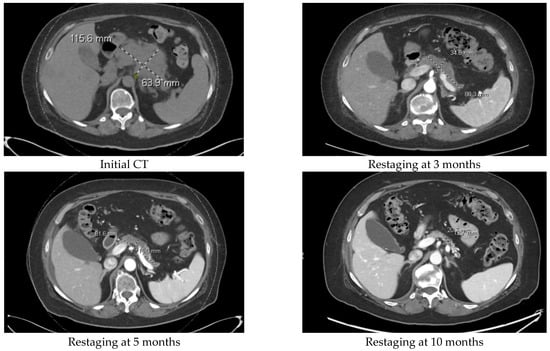

| 58/F | Folfirinox 1 mo switch when RET-1 gene fusion identified. | Selpercatinib. Continuing to show PR. | 26 | |